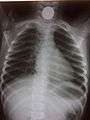

Chest radiograph showing a Venezuelan 25 cent coin lodged in the upper esophagus of a 9-year-old girl.

A coin seen on AP CXR in the esophagus

A coin seen on lateral CXR in the esophagus

If the person who swallowed the foreign body is doing well, usually an x-ray image will be taken which will show any metal objects, and this will be repeated a few days later to confirm that the object has passed all the way through the digestive system. Also it needs to be confirmed that the object is not stuck in the airways, in the bronchial tree.